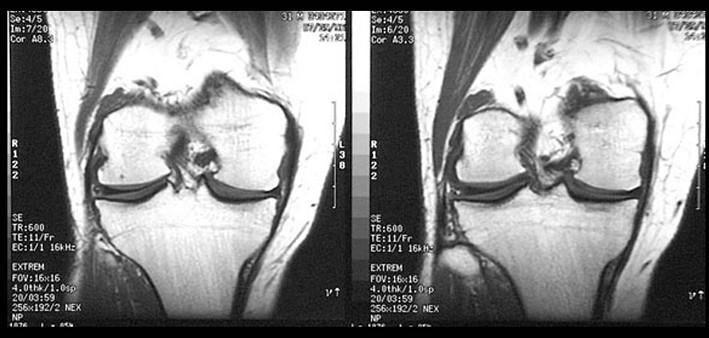

请根据所提供的图像,选择最佳选项是 ( )A、半月板损伤B、半月板囊变C、桶状半月板D、半月板黏液样变E、盘状半月板

问题 请根据所提供的图像,选择最佳选项是 ( )

选项 A、半月板损伤 B、半月板囊变 C、桶状半月板 D、半月板黏液样变 E、盘状半月板

答案 E